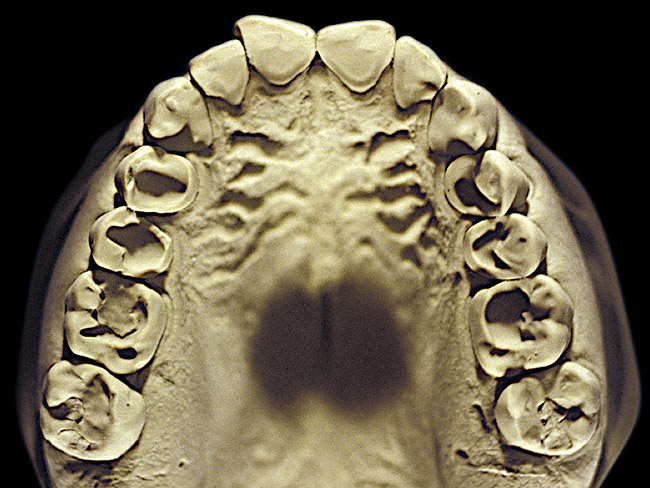

Figure 7  Moderate NCLTS from toothpaste, maxillary arch.

Figure 7

Figure 7 and Figure 8 are examples of NCLTS resulting from toothpaste. Upon examination, one could see that the overall anatomical detail of the teeth was faded with a sandblasted appearance. A closer view of the facial surfaces (Figure 9 and Figure 10) illustrates this to a greater degree and one can observe that the normal intricate facial anatomy was completely missing. It is interesting to note there was no cervical recession of the gingiva, even though every surface of every tooth had been abraded. This is due to the fact that this patient had always used a soft, round-ended filament toothbrush.21-22 This patient's sole desire regarding her oral hygiene was to get her teeth whiter.